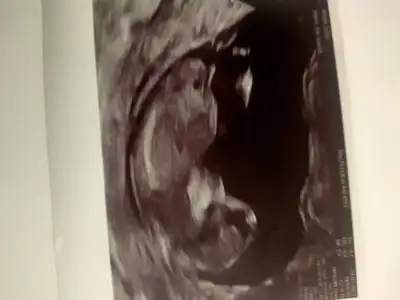

Hayırlı haberler al inşallahKızlar yarın randevum var lütfen dua edin göstersin kendini de öğrenelim cinsiyetini miniğin![]()

Ayy gözün aydın nasıl sevindiimmmDilos6342 cok sukur rdvu aldim yarina

8.45 de Of icim ferahlar gorurum de insallah hersey yolundadir

InsallahAyy gözün aydın nasıl sevindiimmmhadi bebisini gör gel yarın hiç biseyde yoktur eminimm